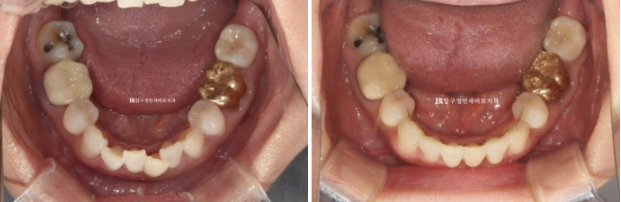

50대 환자분께서 앞니가 점점 뻗치고 틀어져서 교정을 위해 내원하셨습니다.

오래 전 발치교정을 이미 끝냈는데, 나이가 들면서 점점 앞니가 틀어져 앞니 부분교정을 위해 오셨습니다.

위 앞니 두개가 튀어나와있고 회전이 되어있습니다.

정식용어는 아니지만 이것을 나비치아 라고 부릅니다.

이 정도면 인비절라인 라이트로도 충분히 교정이 가능합니다.

걱정하시는 교합도 좋습니다.

23.07~24.05